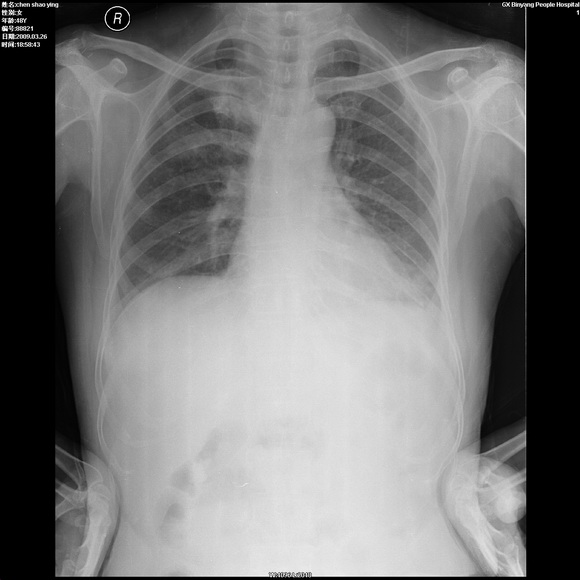

患者,女,48岁,发热伴陈发性咳嗽5天,偶尔痰中带血。体温约38°~40°;白细胞明显减低0.85x10的9次方/升。入院后抗炎、抗痨一周复查病灶明显进展。

右上肺后段实变影,内见支气管气象,肺门未见软组织肿块,气管前方有肿大淋巴结。左下肺见多个类圆形结节影。考虑:1.右上肺后段大叶性肺炎,需进一步检查病原体种类,应多询问病史,条件许可考虑做纤支镜检查2.左下肺结节影性质待定

右上肺炎 左侧支扩伴感染 结节影抗炎后复查

考虑右上肺后段大叶性肺炎不除外结核,伴双肺结节播散灶,希定期复查。

问题是抗炎治疗一个星期后病灶进展。

1.右肺上叶考虑炎症,建议痰培养 2.左肺下叶结节性质待定

右肺片状实变影,左肺结节影,抗炎及抗捞治疗后病灶进展。

我考虑:不能除外肺炎型肺泡癌可能。建议查痰或活检。